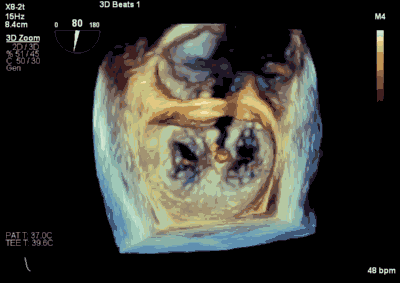

▲ 术前超声检查显示重度二尖瓣反流

患者为66岁老年男性,4个月余前因“急性心肌梗死合并二尖瓣后叶腱索断裂”出现心源性休克,在IABP支持下仍反复发作左心心力衰竭,经过急诊血运重建联合优化药物治疗后症状好转,但术后多次发作严重左心心力衰竭,超声心动图评估二尖瓣反流急性增加至极重度,左房、左室显著扩大。此次主诉“反复胸闷、气促4月余”入院。诊断:心脏瓣膜病 二尖瓣脱垂伴重度关闭不全 二尖瓣后叶腱索断裂 心功能IV级(NYHA分级) 。术前经胸超声心动图示:全心扩大,二尖瓣后叶脱垂、腱索断裂合并重度关闭不全(DMR 4+)。心脏测值:LA 45mm LVD 55mm EF% 61% PASP 82mmHg。经食管超声心动图示:二尖瓣环左右径33mm,反流束缩流颈宽度为5.5mm,EROA 0.67cm2(PISA),舒张期二尖瓣口平均跨瓣压差5mmHg。